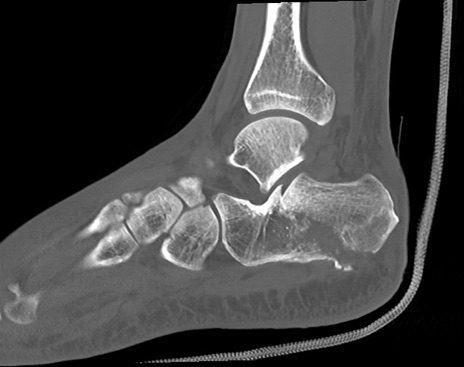

症例37 左足関節CT(矢状断像)

左足関節CT